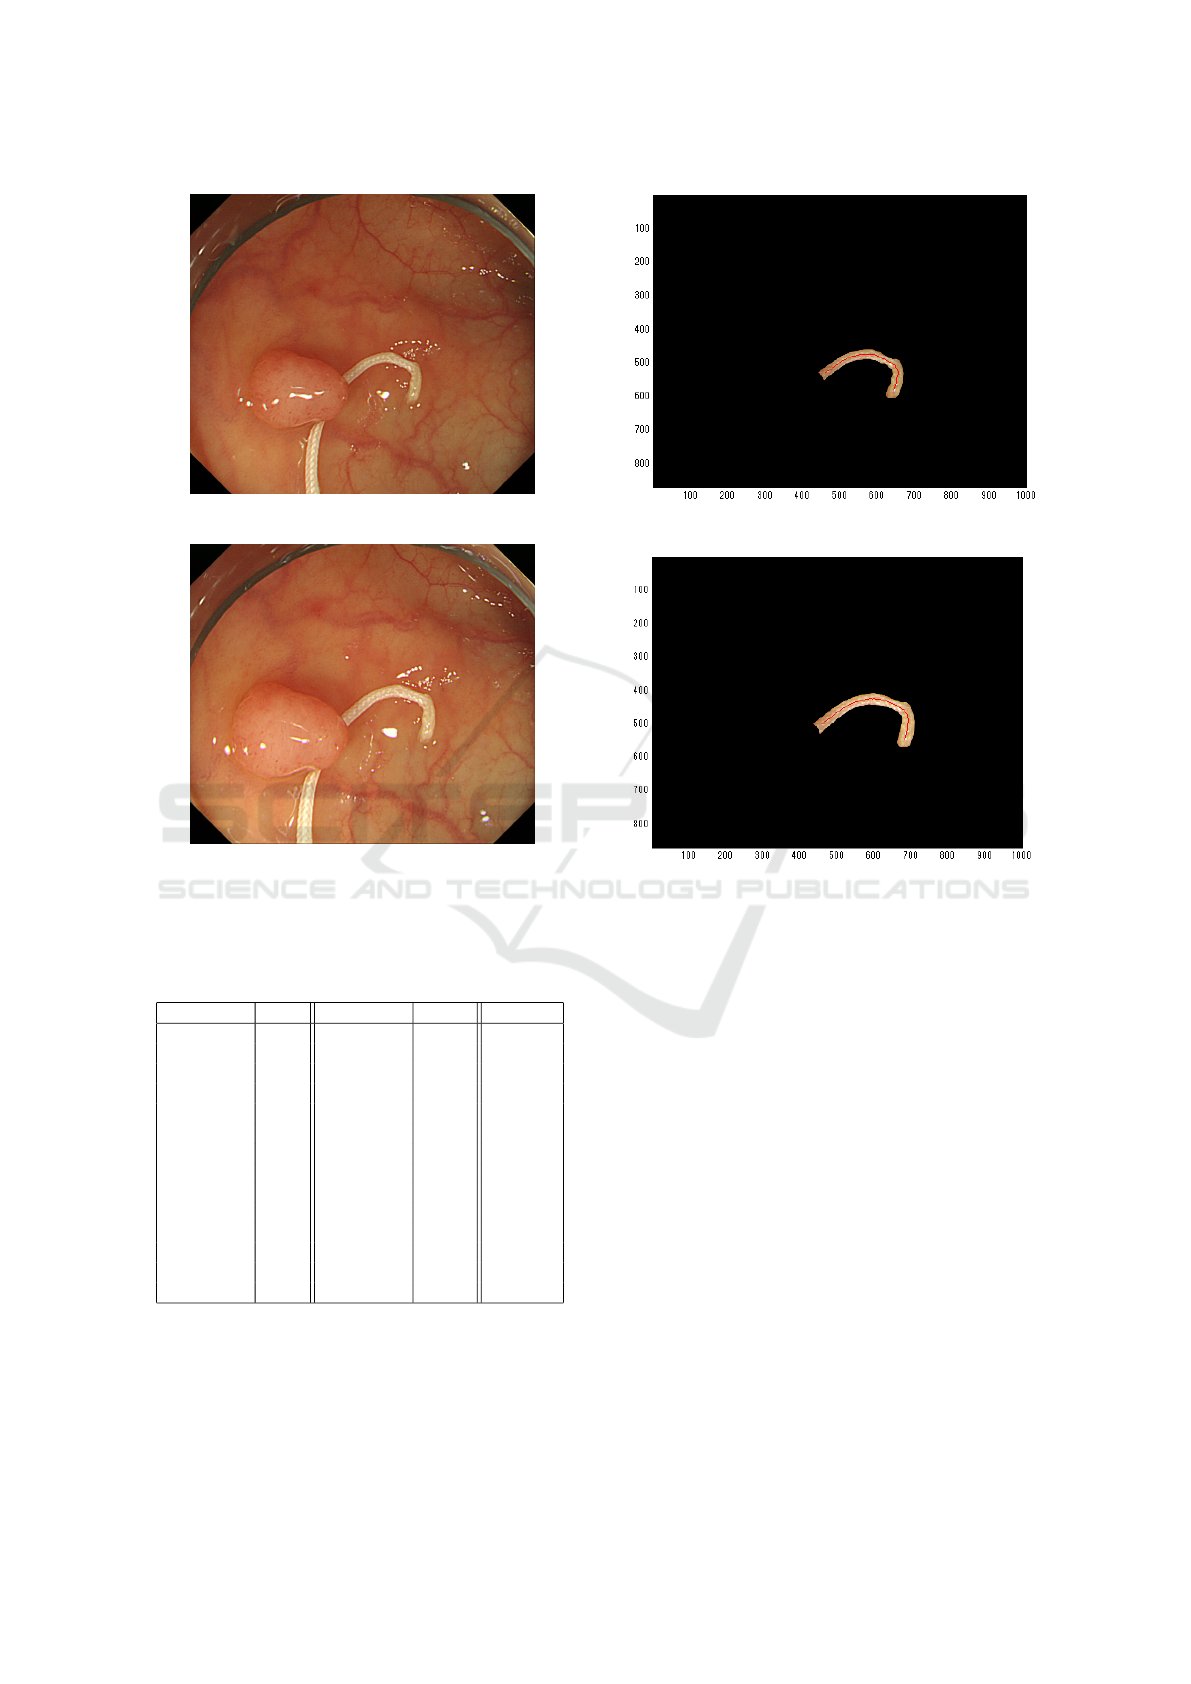

It is shown that the proposed approach is valuable

in the recovery process of polyp and the evaluation is

provided via experiments with real endoscope envi-

ronment. Using the medical suture as a calibration

object is not always useful but the paper extended

the possibility to recover the absolute size and shape

of polyp with further information. Further subject

includes that another cue information instead of the

medical suture is used and the entire purpose is done

with usual endoscope environment.